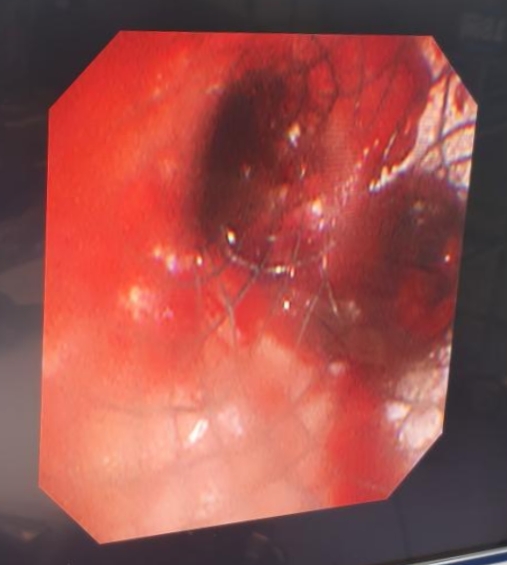

术后支气管镜下显示患者支气管显著通畅。

支气管镜下见气道内已置入支架,气道通气良好。